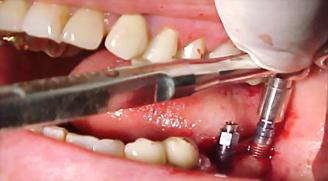

Figura n°7. Esta fotografia está mostrando a última broca usada (3,15mm) passando pela abertura do guia cirúrgico, antes da aplicação da broca especial do sistema Conect, para

implante de Ø4,3 X 10,0mm. É importante que a última broca de abertura fique na posição o mais ideal possível, pois a posição final, praticamente não pode ser alterada pela última broca do Sistema Conect.